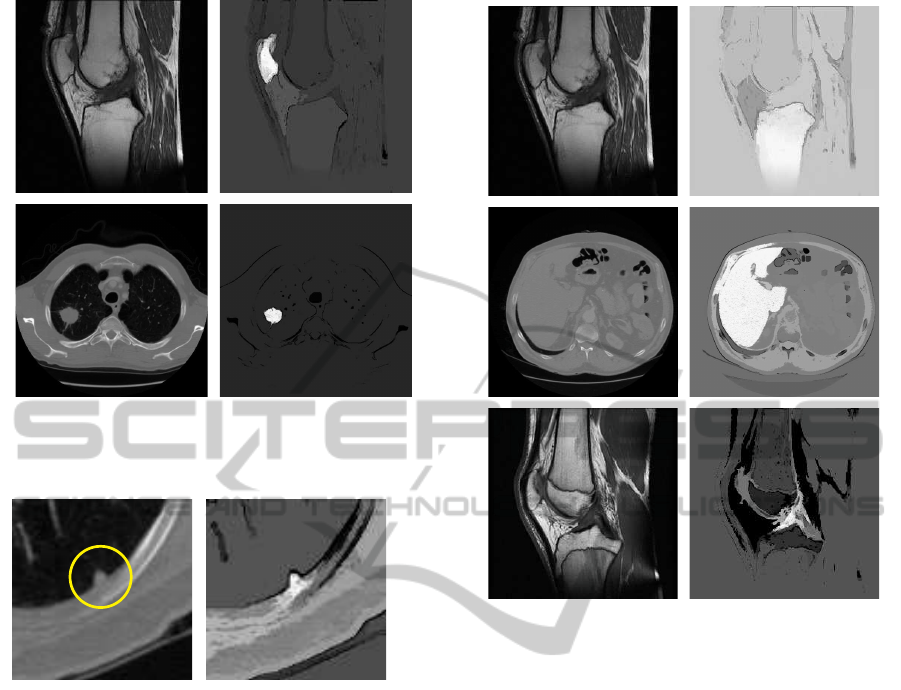

In the computer aided diagnosis, the image seg-

mentation is often used as a first step in an au-

tomated case analysis. As such, it benefits from

the fuzzy notion provided by the fuzzy connected-

ness. After 15 years since being announced the fuzzy

connectedness-based algorithms appeared in multiple

segmentation applications and programming environ-

ments (e.g. note the specified FC filters in the ITK –

Insight Toolkit – environment). The properly defined

connectedness between points within objects is help-

ful in achieving precise and reliable delineation of the

structures. Sometimes the FC analysis is sufficient as

a standalone segmentation method; other times it pro-

vides just the most accurate part of a larger process.